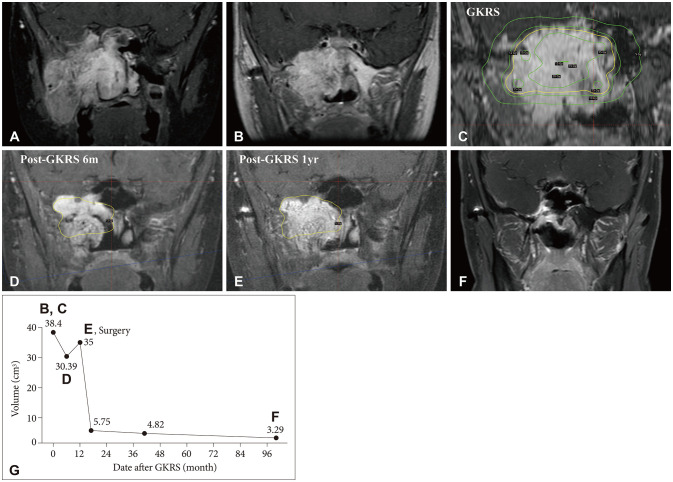

Juvenile nasopharyngeal angiofibroma (JNA) is a rare, benign, but locally aggressive tumor that typically affects adolescent males. While surgical resection is the standard treatment, achieving total resection is often challenging in advanced-stage tumors with intracranial extension, resulting in high recurrence rates. Gamma knife radiosurgery (GKRS) has been suggested as a potential adjuvant or salvage therapy, but evidence remains limited. In this study, we report three pediatric cases of advanced-stage JNA treated with GKRS following incomplete surgical resection. Two patients demonstrated durable local tumor control with a significant reduction in tumor size until 2 and 12 years after GKRS. The other patient with partial coverage of tumor by prescription isodose 12 Gy showed a reduction of tumor volume at 6 months but subsequent progression at 1 year. No GKRS-related complications were observed during the follow-up period. Our findings suggest that GKRS appears to be a potentially safe and effective treatment modality for residual or recurrent JNAs. Fractionated or staged GKRS combined with surgery may be a preferable strategy for large tumors in which extensive surgery alone, conventional radiotherapy, or single-fraction radiosurgery may be associated with increased morbidity in pediatric populations.